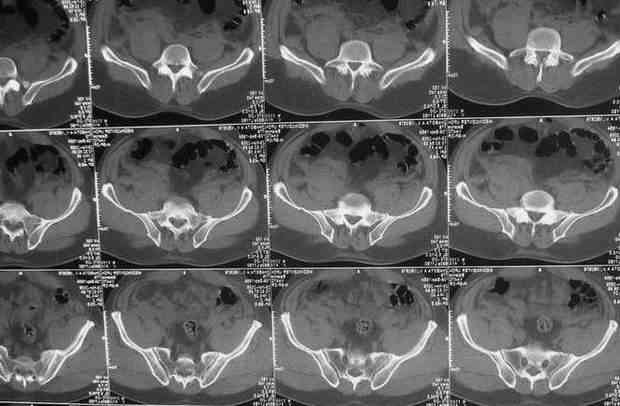

Уважаемые коллеги.У больного оскольчатые переломы левых лонной и седалищной костей со смещением, разрывом симфиза и распространением линии перелома на вертлужную впадину; переломы крыла левой подвздошной кости и правой боковой массы крестца без смещения; разрыв уретры.За последние годы пациент 6 раз оперирован на передней брюшной стенке (гнойный аппендицит срединным доступом, вентральная послеоперационная грыжа и паховые грыжи с обеих сторон, оперированные по 2 раза каждая). Остались 3 грубых втянутых рубца после этих операций. В настоящее время имеются 2-сторонние паховомошоночные грыжи (на одной из КТ-грамм указаны стрелками), из которых левая - значительных размеров. Мошонка огромная, однако, не напряженная. Состояние больного на сегодняшний день относительно удовлетворительное, кровопотеря компенсирована, мочевой пузырь катетеризирован.Прошу мнения сообщества по следующим вопросам: выполнять ли в таких условиях остеосинтез? Если да, то в какой последовательности (отдельно или одним этапом с герниотомией)? Объем остеосинтеза? Доступ?